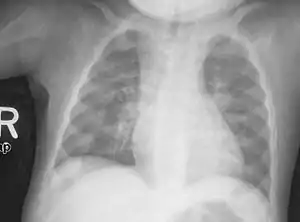

Signs and symptoms of dietary deficiency rickets can include bone tenderness, and a susceptibility for bone fractures, particularly greenstick fractures.[10] Early skeletal deformities can arise in infants such as soft, thinned skull bones – a condition known as craniotabes,[11][12] which is the first sign of rickets; skull bossing may be present and a delayed closure of the fontanelles.

Young children may have bowed legs and thickened ankles and wrists;[13] older children may have knock knees.[10] Spinal curvatures of kyphoscoliosis or lumbar lordosis may be present. The pelvic bones may be deformed. A condition known as rachitic rosary can result as the thickening caused by nodules forming on the costochondral joints. This appears as a visible bump in the middle of each rib in a line on each side of the body. This somewhat resembles a rosary, giving rise to its name. The deformity of a pigeon chest[10] may result in the presence of Harrison's groove.

An X-ray or radiograph of an advanced patient with rickets tends to present in a classic way: the bowed legs (outward curve of long bone of the legs) and a deformed chest. Changes in the skull also occur causing a distinctive "square headed" appearance known as "caput quadratum".[14] These deformities persist into adult life if not treated. Long-term consequences include permanent curvatures or disfiguration of the long bones, and a curved back.[15]